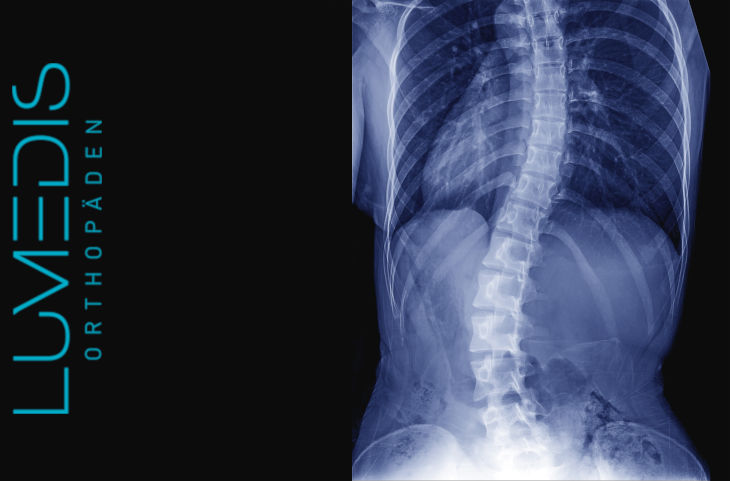

Röntgenbild einer degenerativen LWS Skoliose

Röntgenbild der gesamten Wirbelsäule mit starker Skoliose